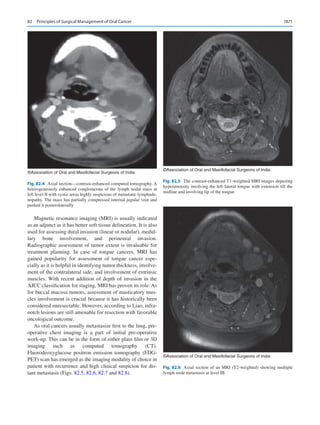

Principles of Surgical Management of Oral Cancer��������������������������������������������� 1869

Sushma Mehta and Moni Abraham Kuriakose